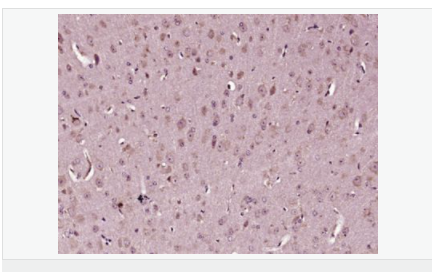

| 產品應用 | WB=1:500-2000 ELISA=1:5000-10000 IHC-P=1:100-500 IHC-F=1:100-500 Flow-Cyt=1μg /test IF=1:100-500 (石蠟切片需做抗原修復) not yet tested in other applications. optimal dilutions/concentrations should be determined by the end user. |

| 產品介紹 | Caspases are a family of cysteine proteases that are key mediators of programmed cell death or apoptosis. The precursor form of all caspases is composed of a prodomain, and large and small catalytic subunits. The active forms of caspases are generated by several stimuli including ligand-receptor interactions, growth factor deprivation and inhibitors of cellular functions. All known caspases require cleavage adjacent to aspartates to liberate one large and one small subunit, which associate into a2b2 tetramer to form the active enzyme. Gene for Caspase 3 also known as Yama, CPP32, and apopain codes for a 32-kDa protein. Caspase 3 cleaves the death substrate poly(ADP-ribose) polymerase (PARP) to a specific 85 kDa form observed during apoptosis and is inhibitable by the CrmA protein. Other Caspase 3 substrates include DNA-PK, actin, GAS2, and procaspase-6, etc. Caspase 3 is activated by cleavage events at Asp-28/Ser-29 (between N-terminal pro-domain) and Asp-175/Ser-176 (between large and small subunits) to generate a large subunit of 17-kDa and a small subunit of 12-kDa. Function: Involved in the activation cascade of caspases responsible for apoptosis execution. At the onset of apoptosis it proteolytically cleaves poly(ADP-ribose) polymerase (PARP) at a '216-Asp-|-Gly-217' bond. Cleaves and activates sterol regulatory element binding proteins (SREBPs) between the basic helix-loop-helix leucine zipper domain and the membrane attachment domain. Cleaves and activates caspase-6, -7 and -9. Involved in the cleavage of huntingtin. Triggers cell adhesion in sympathetic neurons through RET cleavage. Subunit: Heterotetramer that consists of two anti-parallel arranged heterodimers, each one formed by a 17 kDa (p17) and a 12 kDa (p12) subunit. Interacts with BIRC6/bruce. Subcellular Location: Cytoplasm. Tissue Specificity: Highly expressed in lung, spleen, heart, liver and kidney. Moderate levels in brain and skeletal muscle, and low in testis. Also found in many cell lines, highest expression in cells of the immune system. Post-translational modifications: Cleavage by granzyme B, caspase-6, caspase-8 and caspase-10 generates the two active subunits. Additional processing of the propeptides is likely due to the autocatalytic activity of the activated protease. Active heterodimers between the small subunit of caspase-7 protease and the large subunit of caspase-3 also occur and vice versa. S-nitrosylated on its catalytic site cysteine in unstimulated human cell lines and denitrosylated upon activation of the Fas apoptotic pathway, associated with an increase in intracellular caspase activity. Fas therefore activates caspase-3 not only by inducing the cleavage of the caspase zymogen to its active subunits, but also by stimulating the denitrosylation of its active site thiol. Similarity: Belongs to the peptidase C14A family. SWISS: P55213 Gene ID: 836 Database links: Entrez Gene: 836 Human Entrez Gene: 12367 Mouse Entrez Gene: 100008840 Rabbit Omim: 600636 Human SwissProt: P42574 Human SwissProt: P70677 Mouse SwissProt: Q8MJC3 Rabbit Unigene: 141125 Human Unigene: 34405 Mouse Unigene: 10562 Rat Important Note: This product as supplied is intended for research use only, not for use in human, therapeutic or diagnostic applications. |